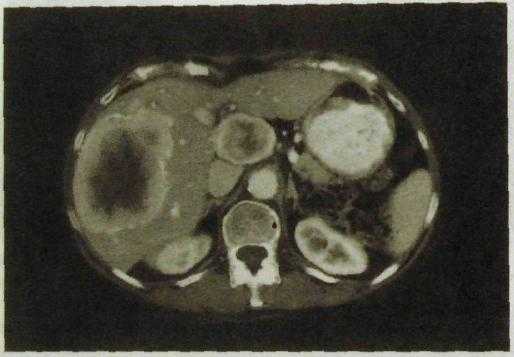

Диффузные поражения печени. Точная диагностика диффузных поражений основывается на анамнестических и клинических данных, результатах биохимических исследований и в ряде случаев пункционной биопсии печени. Лучевые методы обычно играют лишь вспомогательную роль. Исключением является жировой гепатоз. Жир поглощает рентгеновское излучение хуже, чем остальные мягкие ткани, поэтому тень печени при жировом гепатозе на компьютерных томограммах характеризуется низкой плотностью (рис. Ш.136).

Рве. III. 136. Компьютерная томограмма печени. Жировой гепатоз: низкая плотность печеночной ткани.